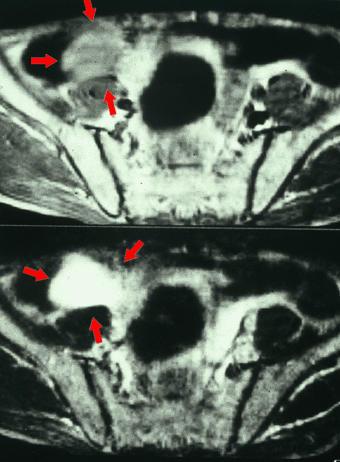

疾患(病理主体)の分類その他の腫瘍/悪性虫垂粘液瘤腫

部位(臓器別)大腸/虫垂

検査方法MRI

病変の最大径(ミリ)40以上